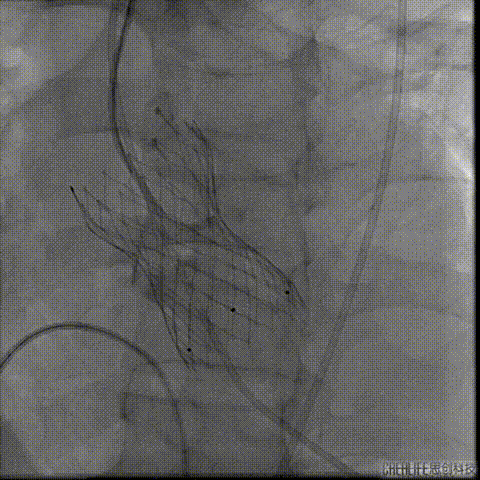

冠脉造影

瓣上造影

猪尾导管位于右窦

严重反流导致造影效果欠佳

左冠显示不清 结构显示不清